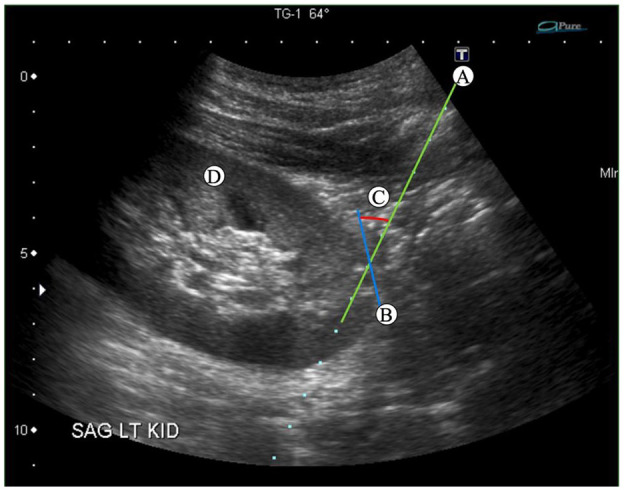

Methods: Technical recommendations included introducing the biopsy needle at a 60° angle, targeting a pole, and avoiding the vascular medulla. Institutional recommendations included microscopic screening for all biopsies, limiting the number of radiologists performing procedures, using a checklist, and restricting computed tomography (CT)-guided biopsies to exceptional cases. Multivariate regression analysis assessed biopsy outcomes before and after the recommendations, controlling for known confounders while at the same time refining factors associated with fewer complications and greater diagnostic yield.

Abstract Image